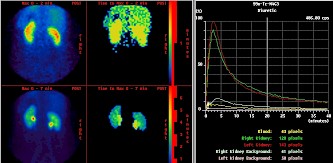

Bild rechts: Auswertungssoftware für eine MAG3 gestützte Nierenszintigrafie

Danke für die Errinerung. :)Heute verwenden wir fast ausschließlich 99m-Tc-MAG-3 für die Nierenszintigraphie. Am häufigsten ist die Fragestellung einer Abflüßstörung und eingeborene Fehlbildungen der Nieren. Zweithäufig - seitengetrennte Nierenfunktionsbeurteilung vor Radiatio oder OP.Seltener kommen die Nierenspender. Welche Fehlerquellen sind bei der Untersuchung zu beachten und wie konnte man die Fehlern vermeiden?